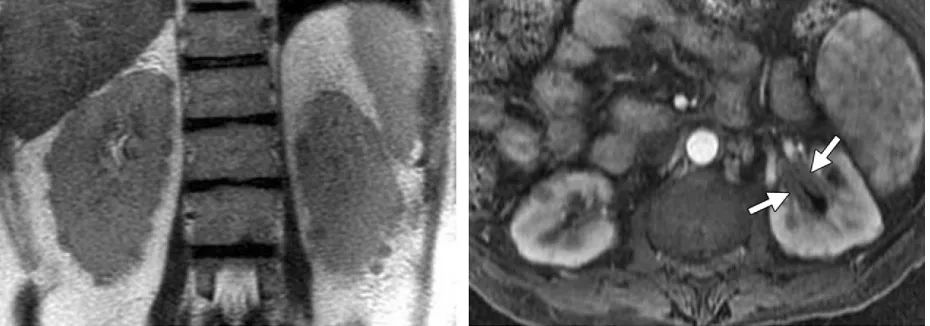

肾脏受累

肾脏受累治疗后